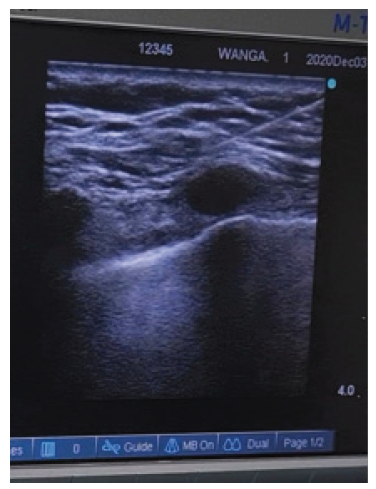

A 32-year-old woman (163 cm, 60 kg) came to Wangaya Hospital with abcess and mass in her left breast that was identified by the ultrasound imaging (Fig. 1). Patient was diagnosed with left breast tumor suspect invasive ductal carcinoma. She had no medical history and scheduled for lumpectomy and biopsy. Ultrasound guided Pecs II block was considered as the anesthesia technique for this surgery. ASA standard monitoring was placed (blood pressure monitor, pulse oxymetri, electrocardiogram), and patient was given premedication with 2 mg of intravenous midazolam. Patient positioned in a supine position with abduction 90o of left arm. Supplemental oxygen was provided by nasal cannule (4 L/min). The left breast and axillary regions were cleaned using iodine. Under aseptic condition, ultrasound probe was placed under the lateral third of the left clavicula, identifiying the third and fourth ribs. Local anesthetic with 2% lidocaine was infiltrated at the puncture site.

Figure 1. Ultrasound imaging 1.07 x 1.08 cm and 0.5 x 0.7 cm multiple hypoechoic mass on left breast